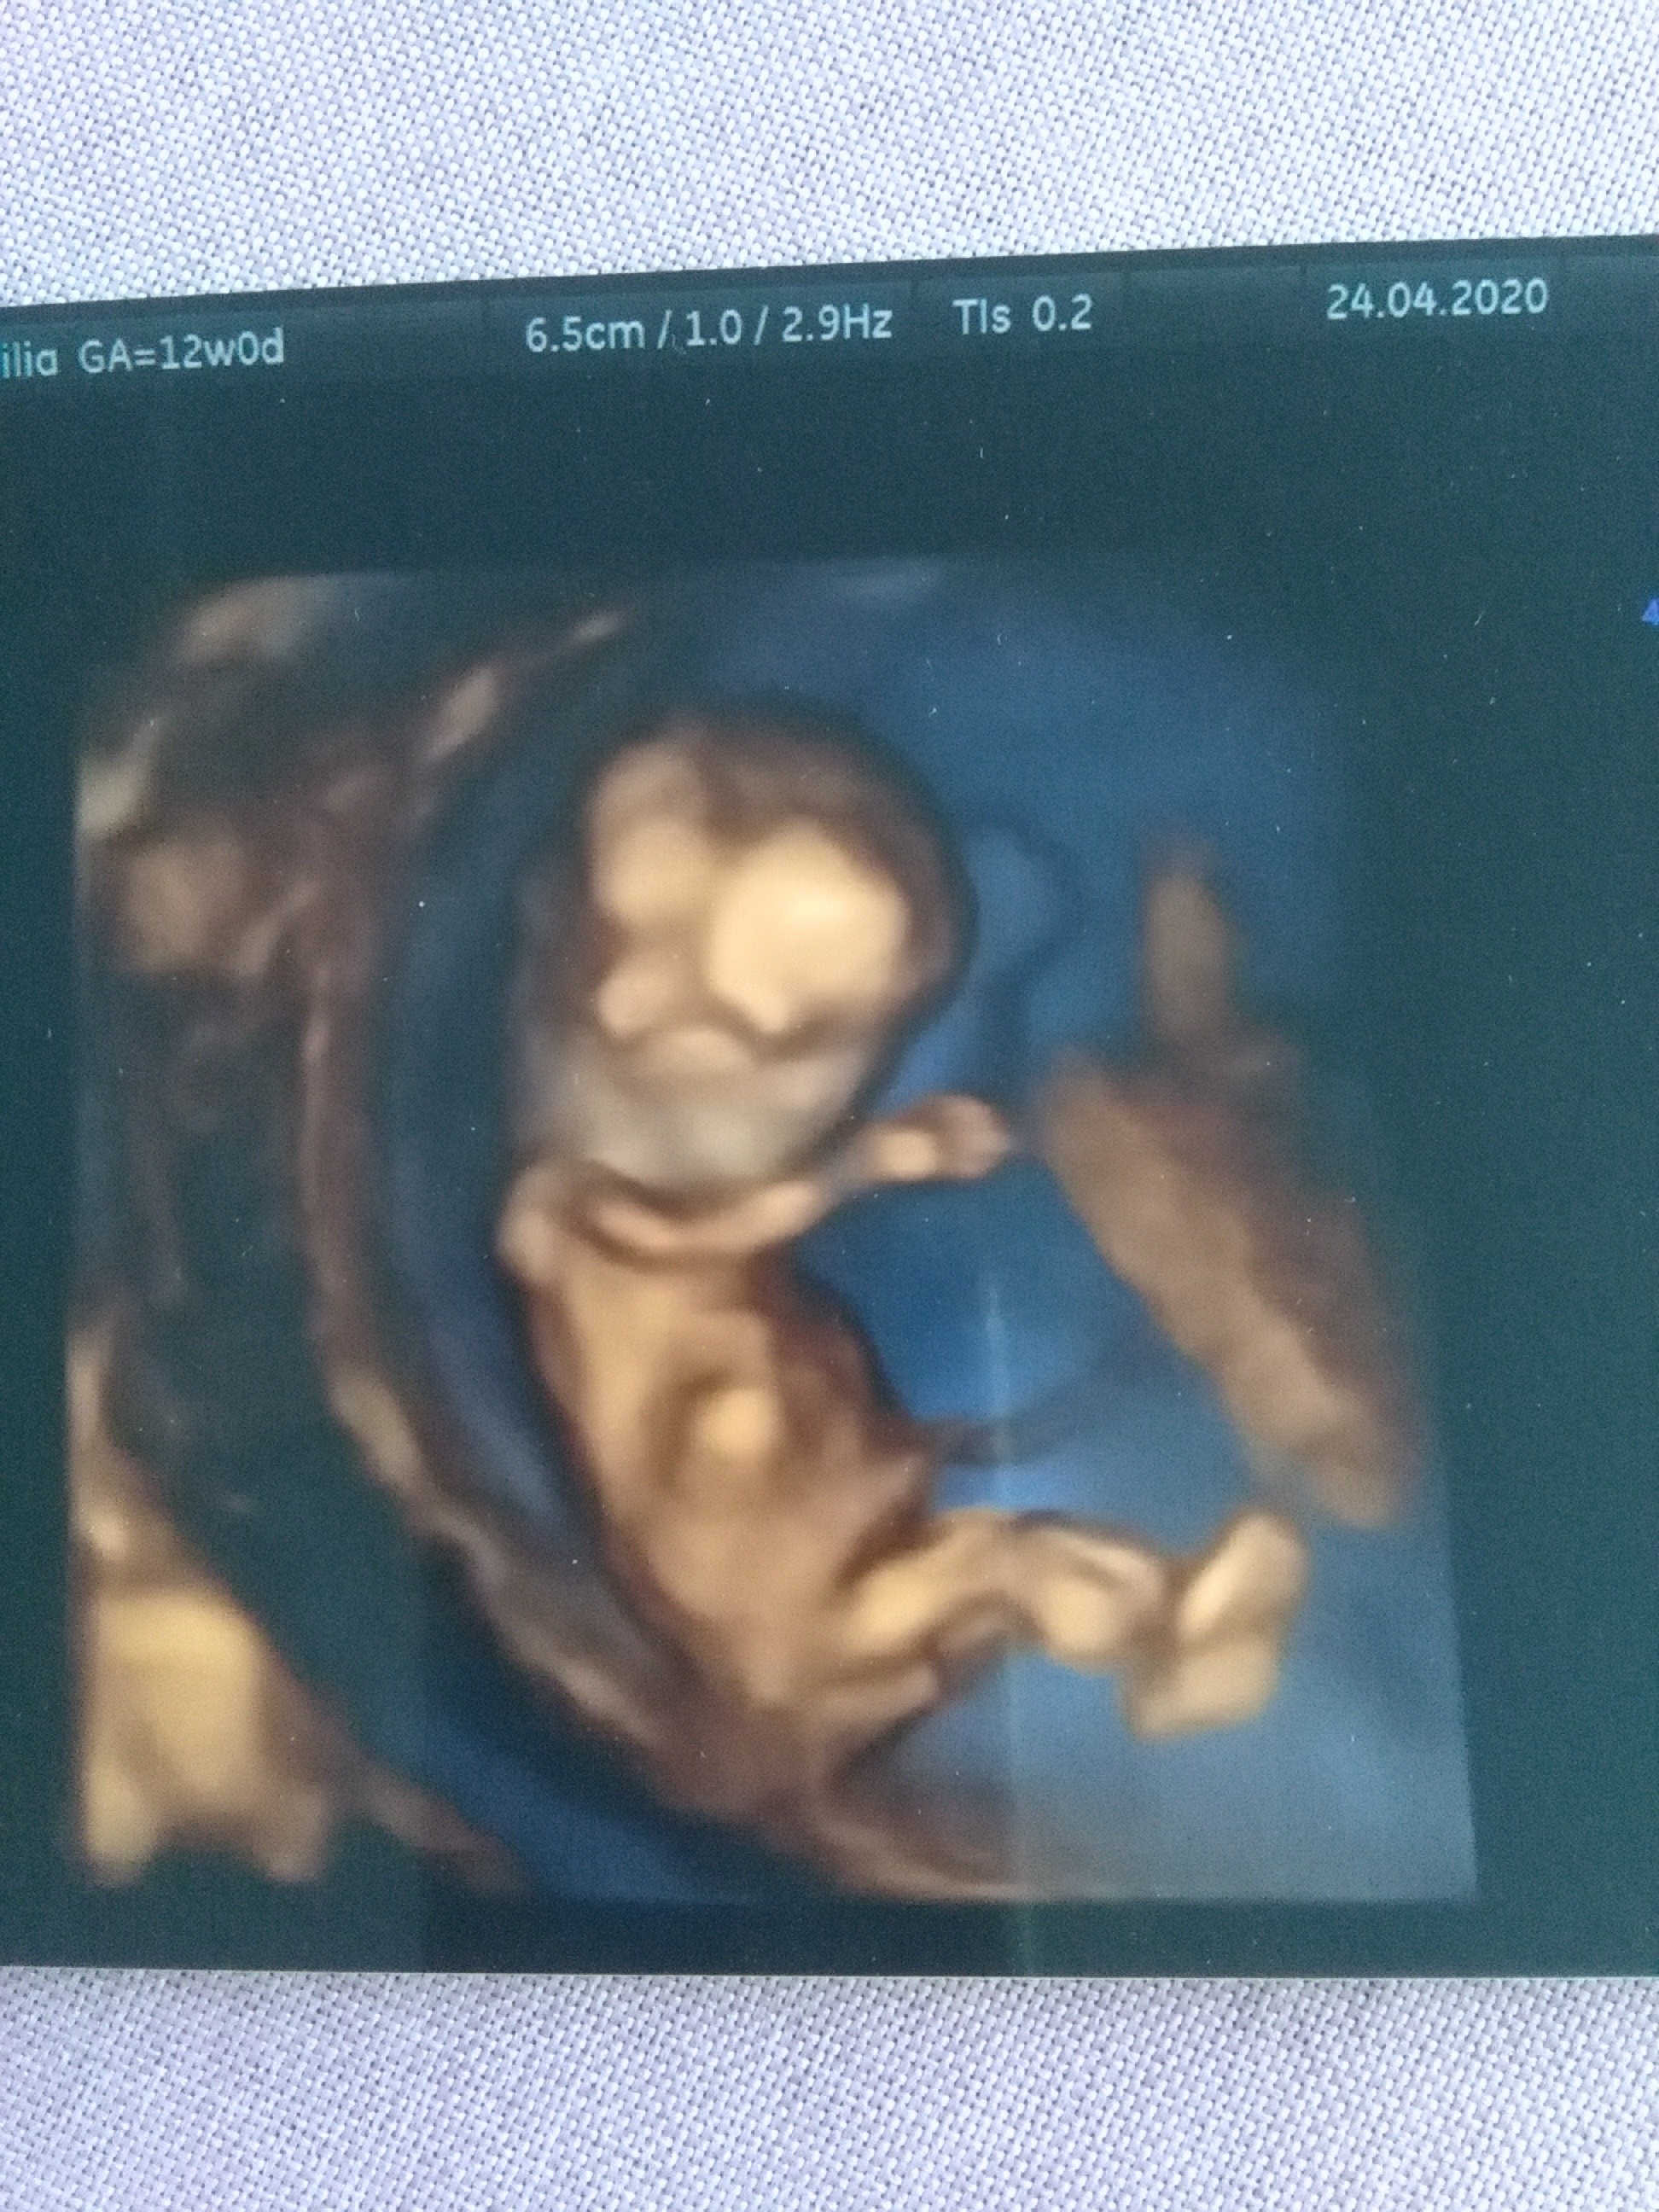

Cieszę się ze z dzidzia wszystko dobrzeI ja też dzisiaj po prenatalnym. Zanim lekarz zaczął to serce mi tak mocno biło że masakra. Miałam robione przez brzuch i wszystko ładnie było widać. Dzidziuś trochę większy niż na dzisiejszy wiek 12+0 mierzy 56,6 mm czyli 4 dni większy. Szerokość główki 17,5mm akcja serduszka 165/min obraz prawidłowy bez cech niedomykalności zastawki. Prawidłowa fala tętna żylnego kość nosowa widoczna przezierność karkowa 1,0mm zarys główki tułowia i kończyn prawidłowy przy pępowinie nie ma nic niepokojącego bo lekarz mówi że nieraz zdarzaja się jakieś przepuchliny czy coś u nas nie ma. Mówi że decyzja o pappa należy do mnie ale wg USG wszystko w jak najlepszym porządku. Dzidziuś ładnie się ruszał i współpracował ☺ mówi że wyrostek płciowy jest widoczny ale nie będzie narazie nic sugerował bo to może się zmienić. No i dostałam filmik na płytce i zdjęcie w 3d a tego się wogole nie spodziewałam